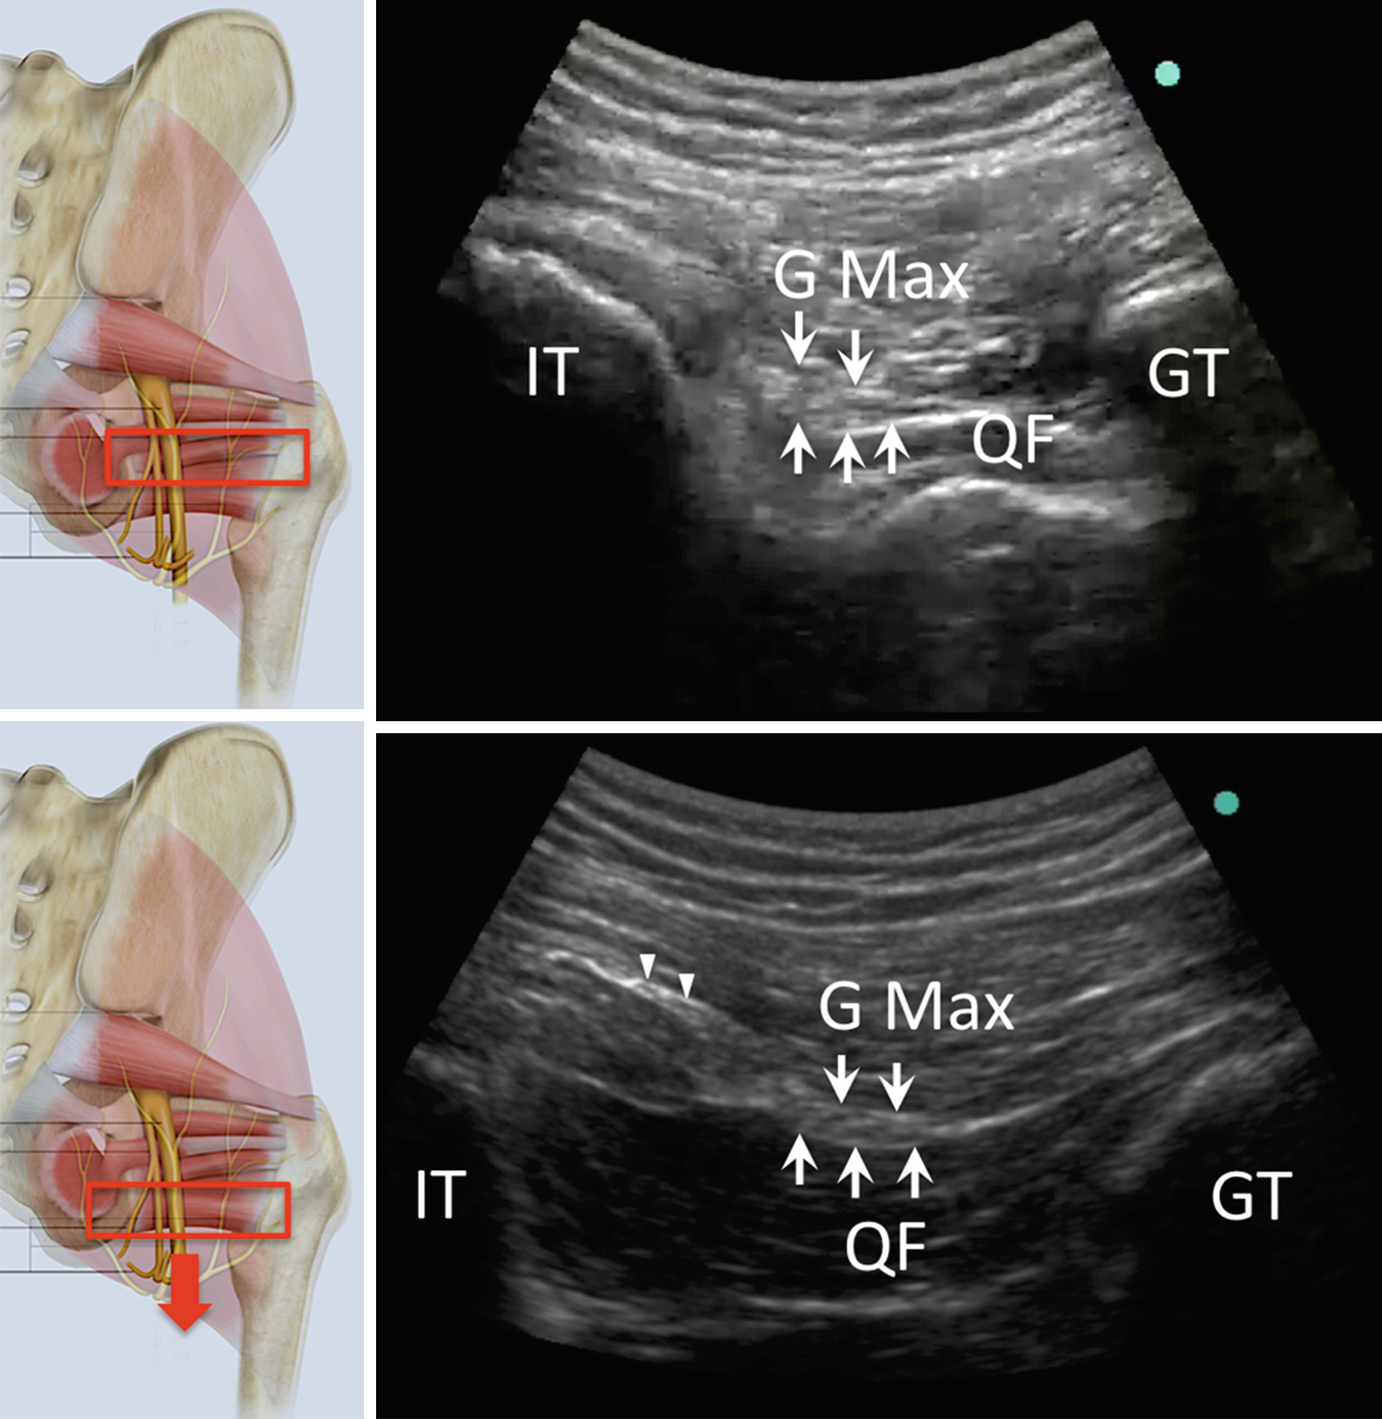

Ultrasound-guided transgluteal TG PNI has been described to reach the pudendal nerve in the plane between the sacrotuberous and sacrospinous ligaments. This technique has many advantages such as visualization of the substantial structures pudendal artery and the sciatic nerve without radiation exposure it enables real-time images.

After standardized general anesthesia the anesthesiologist performed pudendal nerve block under ultrasound guidance with out of plane approach and evaluated the visualization of anatomical structures ischial tuberosity rectum and pudendal artery of the needle and of the local anesthetic spread. Ultrasound-guided pudendal nerve block can also be used as a diagnostic tool when performing differential neural blockade on an anatomic basis in the evaluation of pelvic pain as well as in a prognostic manner to determine the degree of neurologic impairment the patient will suffer when destruction of the pudendal nerve is being considered or when there is a possibility that the nerve may. Some studies block the pudendal nerve in the plane between sacrospinous and sacrotuberous ligaments at the ischial spine level by ultrasound- and CT-scan-guided technique.